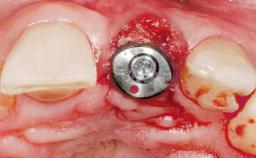

Late Flapless Placement of an Implant in a Maxillary Left Central Incisor Site

Type of Implants One-Piece

Attachment One-Piece